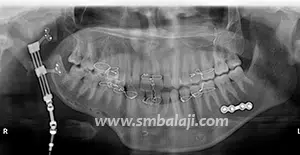

The goal of treatment in hemifacial microsomia is to elongate the deficient jaw bone to restore facial symmetry and correct the slanting bite (occlusion). To achieve this, an advanced and effective treatment technique is distraction osteogenesis. This is a new technique for regenerating new bone by slow, progressive stretching of the bone, without requiring a bone graft.

The jaw bone on the deficient side is cut. A sophisticated device called distractor is placed such that the two arms of the device are fixed to the two segments of jaw bone. After a few days, a screw attached to the distractor is turned gradually, ideally at a rate of 1 mm per day. When this is done, the two cut segments move apart and new bone is formed in the resultant gap. After the new bone is stabilized, the distractor device is removed.

Subsequently, the jaw bone is lengthened to the desired amount correcting the asymmetry of the face. This is a powerful tissue engineering technique for generating unlimited bone.